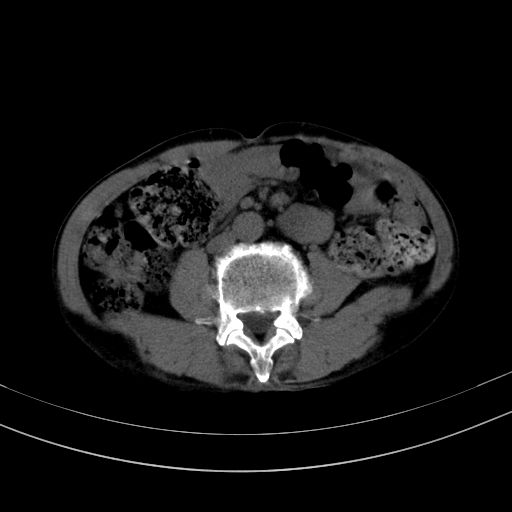

以下是引用37度在2010-1-9 14:37:00的发言:[br]1.双肾囊肿,左肾积水结石,.胆总管轻度扩张;[br]2.病灶在腹膜外,考虑纤维瘤。

以下是引用dyqct在2010-1-9 17:56:00的发言:[br]考虑:1.双肾囊肿,左肾积水结石、旋转不良。[br] 2.右侧腹直肌血肿或纤维瘤。[br]肠道准备不好。做个增强。